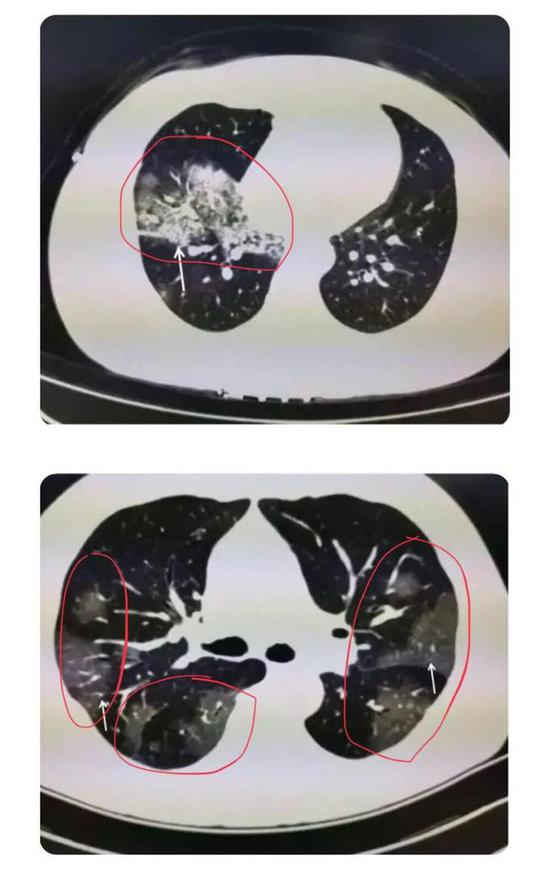

下图是新冠肺炎患者在做肺部CT时的图像,肉眼可见的红色圈内或白色箭头所指区域,相较于肺部其他正常部位出现了像云雾状磨砂玻璃一样的“病灶”,医学上美其名曰“磨玻璃影”。

▲新冠肺炎患者肺部CT显示磨玻璃影(图片来自网络)

根据感染程度不同,有的仅单侧肺出现这种磨玻璃影,还有的双侧都有。磨玻璃影可以累及一个肺叶,也可同时累及多个肺叶。

▲上面的图:单侧肺出现磨玻璃影,累及一个肺叶; ▲下面的图:双侧肺均出现磨玻璃影,累及多个肺叶(图片来自网络)